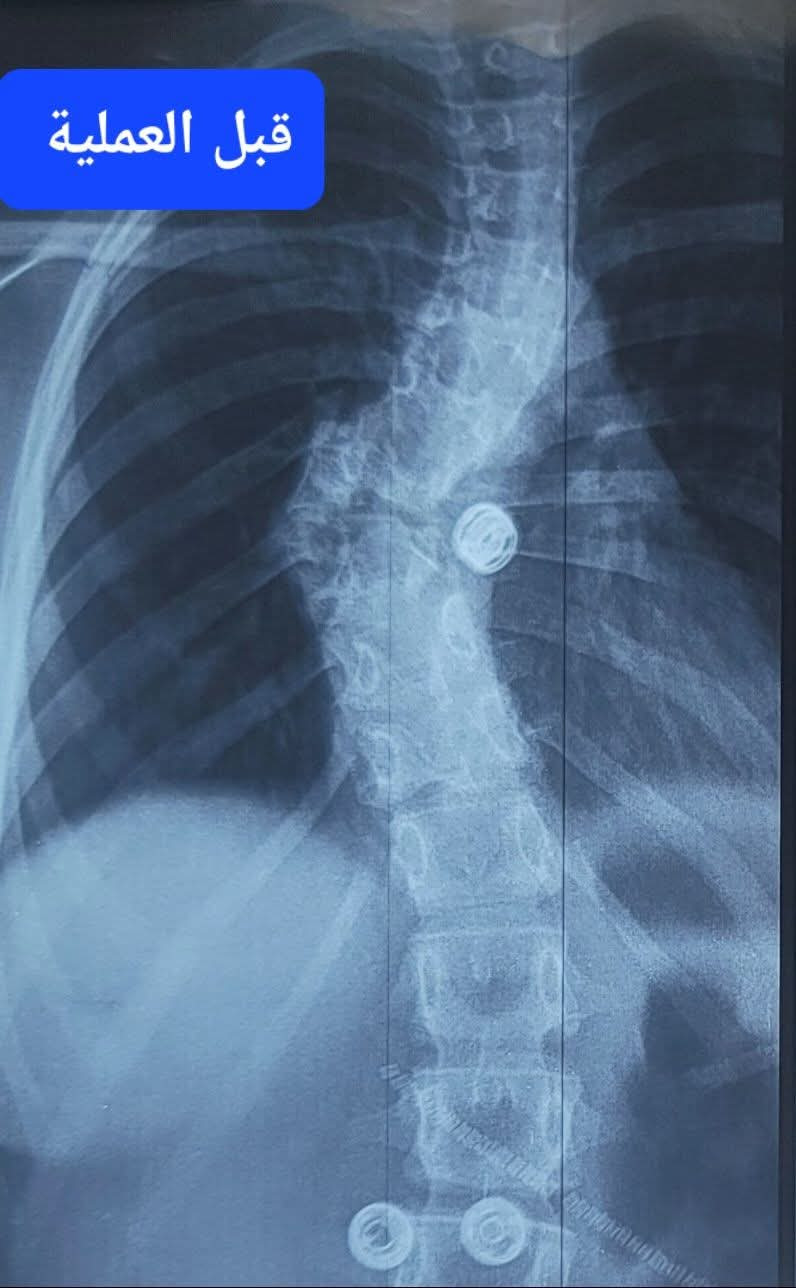

وكانت الطفلة قد وُلدت بعيب خلقي نادر في الفقرة الصدرية الثامنة، تمثل بوجود نصف فقرة فقط وغياب النصف الآخر، ما تسبب في انحناء أمامي حاد بزاوية 90 درجة، إضافة إلى جنف جانبي معقد، ودوران شديد للفقرات والضلوع، وحدبة بارزة سببت لها آلاماً مزمنة.

العملية شملت تحرير الحبل الشوكي، واستئصال الفقرة المشوّهة مع أجزاء من الفقرتين السابعة والتاسعة، وزراعة فقرة صناعية، إلى جانب تثبيت العمود الفقري بواسطة 18 مسماراً طبياً. كما تميّز التدخل بتصحيح الاعوجاجات المتعددة وإعادة التوازن للعمود الفقري بدرجة قريبة من الوضع الطبيعي.

وأكد الدكتور عمر التركي، إن الطفلة وُلدت بعيب خلقي نادر في الفقرة الصدرية الثامنة، حيث وُجد نصف فقرة فقط مع غياب النصف الآخر، ما أدى إلى نمو غير طبيعي للعمود الفقري، تسبب في انحناء أمامي حاد بزاوية 90 درجة، وجَنَف جانبي معقد، وانزياحات متعددة، إضافة إلى دوران شديد للفقرات وحدبة بارزة.

وأوضح التركي أنه وبعد تشخيص دقيق ودراسة مستفيضة للحالة، قمت - بعون الله وتوفيه - ومعي الفريق الجراحي بعمل العملية النوعية والتي شملت تعديل وتصحيح اعوجاج العمود الفقري المتعدد والمعقد، وتحرير الحبل الشوكي، واستئصال الفقرة المشوّهة مع أجزاء من الفقرتين السابعة والتاسعة، وزراعة فقرة صناعية، وتثبيت العمود الفقري وتعديله بواسطة 18 مسماراً طبياً.